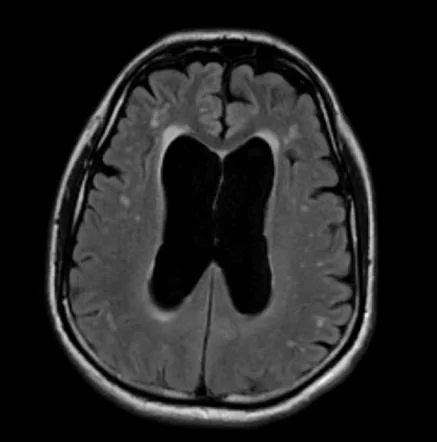

Ο υδροκέφαλος φυσιολογικής πίεσης (Normal Pressure Hydrocephalus – NPH) αναφέρεται σε μια κατάσταση στην οποία οι κοιλίες του εγκεφάλου έχουν αυξημένο μέγεθος, όμως η πίεση του εγκεφαλονωτιαίου υγρού είναι φυσιολογική. Ο NPH είναι επικοινωνών υδροκέφαλος, δηλαδή δεν υπάρχει απόφραξη σε κάποιο σημείο του κοιλιακού συστήματος και διαφοροποιείται από τον αποφρακτικό ή μη επικοινωνούντα υδροκέφαλο, στον οποίο υπάρχει απόφραξη της κυκλοφορίας του εγκεφαλονωτιαίου υγρού (CSF) στο κοιλιακό σύστημα (π.χ. στένωση του υδραγωγού του Sylvius).

- Η μαγνητική τομογραφία (MRI) και η αξονική τομογραφία (CT) χρησιμοποιούνται για να αξιολογήσουν το μέγεθος του κοιλιακού συστήματος (υδροκέφαλος). Η MRI είναι ανώτερη από την CT στην αξιολόγηση των ασθενών με πιθανό NPH επειδή επιτρέπει την ακριβέστερη απεικόνιση του εγκεφάλου και μπορεί παράλληλα να αποκλείσει άλλες πιθανές διαγνώσεις.

Ο όρος υδροκέφαλος ή συχνά και υδροκεφαλία προέρχεται από τις ελληνικές λέξεις ὕδωρ + κεφαλή δηλαδή νερό και κεφάλι. Όπως υποδηλώνει το όνομα, είναι μια κατάσταση στην οποία το κύριο χαρακτηριστικό είναι η υπερβολική συσσώρευση υγρού στον εγκέφαλο. Αν και ο υδροκέφαλος κάποτε ήταν γνωστός ως «νερό στον εγκέφαλο», το «νερό» είναι στην πραγματικότητα εγκεφαλονωτιαίο υγρό (ΕΝΥ) – ένα καθαρό υγρό που περιβάλλει τον εγκέφαλο και το νωτιαίο μυελό. Η υπερβολική συσσώρευση του ΕΝΥ έχει ως αποτέλεσμα τη διεύρυνση των χώρων στον εγκέφαλο που ονομάζονται κοιλίες ή κοιλιακό σύστημα. Αυτή η διεύρυνση μπορεί να δημιουργήσει επιβλαβή πίεση στον εγκέφαλο.

Το κοιλιακό σύστημα αποτελείται από τέσσερις κοιλίες που συνδέονται με στενά περάσματα. Κανονικά, το ΕΝΥ ρέει μέσω των κοιλιών, εξέρχεται σε δεξαμενές (κλειστούς χώρους που χρησιμεύουν ως δεξαμενές) στη βάση του εγκεφάλου, περιβάλλει τις επιφάνειες του εγκεφάλου και του νωτιαίου μυελού και στη συνέχεια επαναρροφάται στην κυκλοφορία του αίματος.

Ο υδροκέφαλος διακρίνεται επίσης σε επικοινωνών ή μή-επικοινωνών (αποφρακτικός). Στον επικοινωνώντα υδροκέφαλο δεν υπάρχει σε κάποιο σημείο του κοιλιακού συστήματος απόφραξη, δηλαδή το εγκεφαλονωτιαίο υγρό μπορεί να κυκλοφορεί ελεύθερα αλλά δεν απορροφάται σωστά. Ο μη-επικοινωνώντας υδροκεφαλός – που ονομάζεται επίσης “αποφρακτικός” υδροκέφαλος – συμβαίνει όταν η ροή του εγκεφαλονωτιαίου υγρόύ φράσσεται κατά μήκος μίας ή περισσοτέρων από τις στενές διόδους που συνδέουν τις κοιλίες. Μία από τις πιο συχνές αιτίες υδροκεφάλου είναι η στένωση του υδραγωγού. Στην περίπτωση αυτή, ο υδροκέφαλος οφείλεται σε στένωση του υδραγωγού του Sylvius, ένα μικρό πέρασμα μεταξύ της τρίτης και της τέταρτης κοιλίας στο κέντρο του εγκεφάλου.